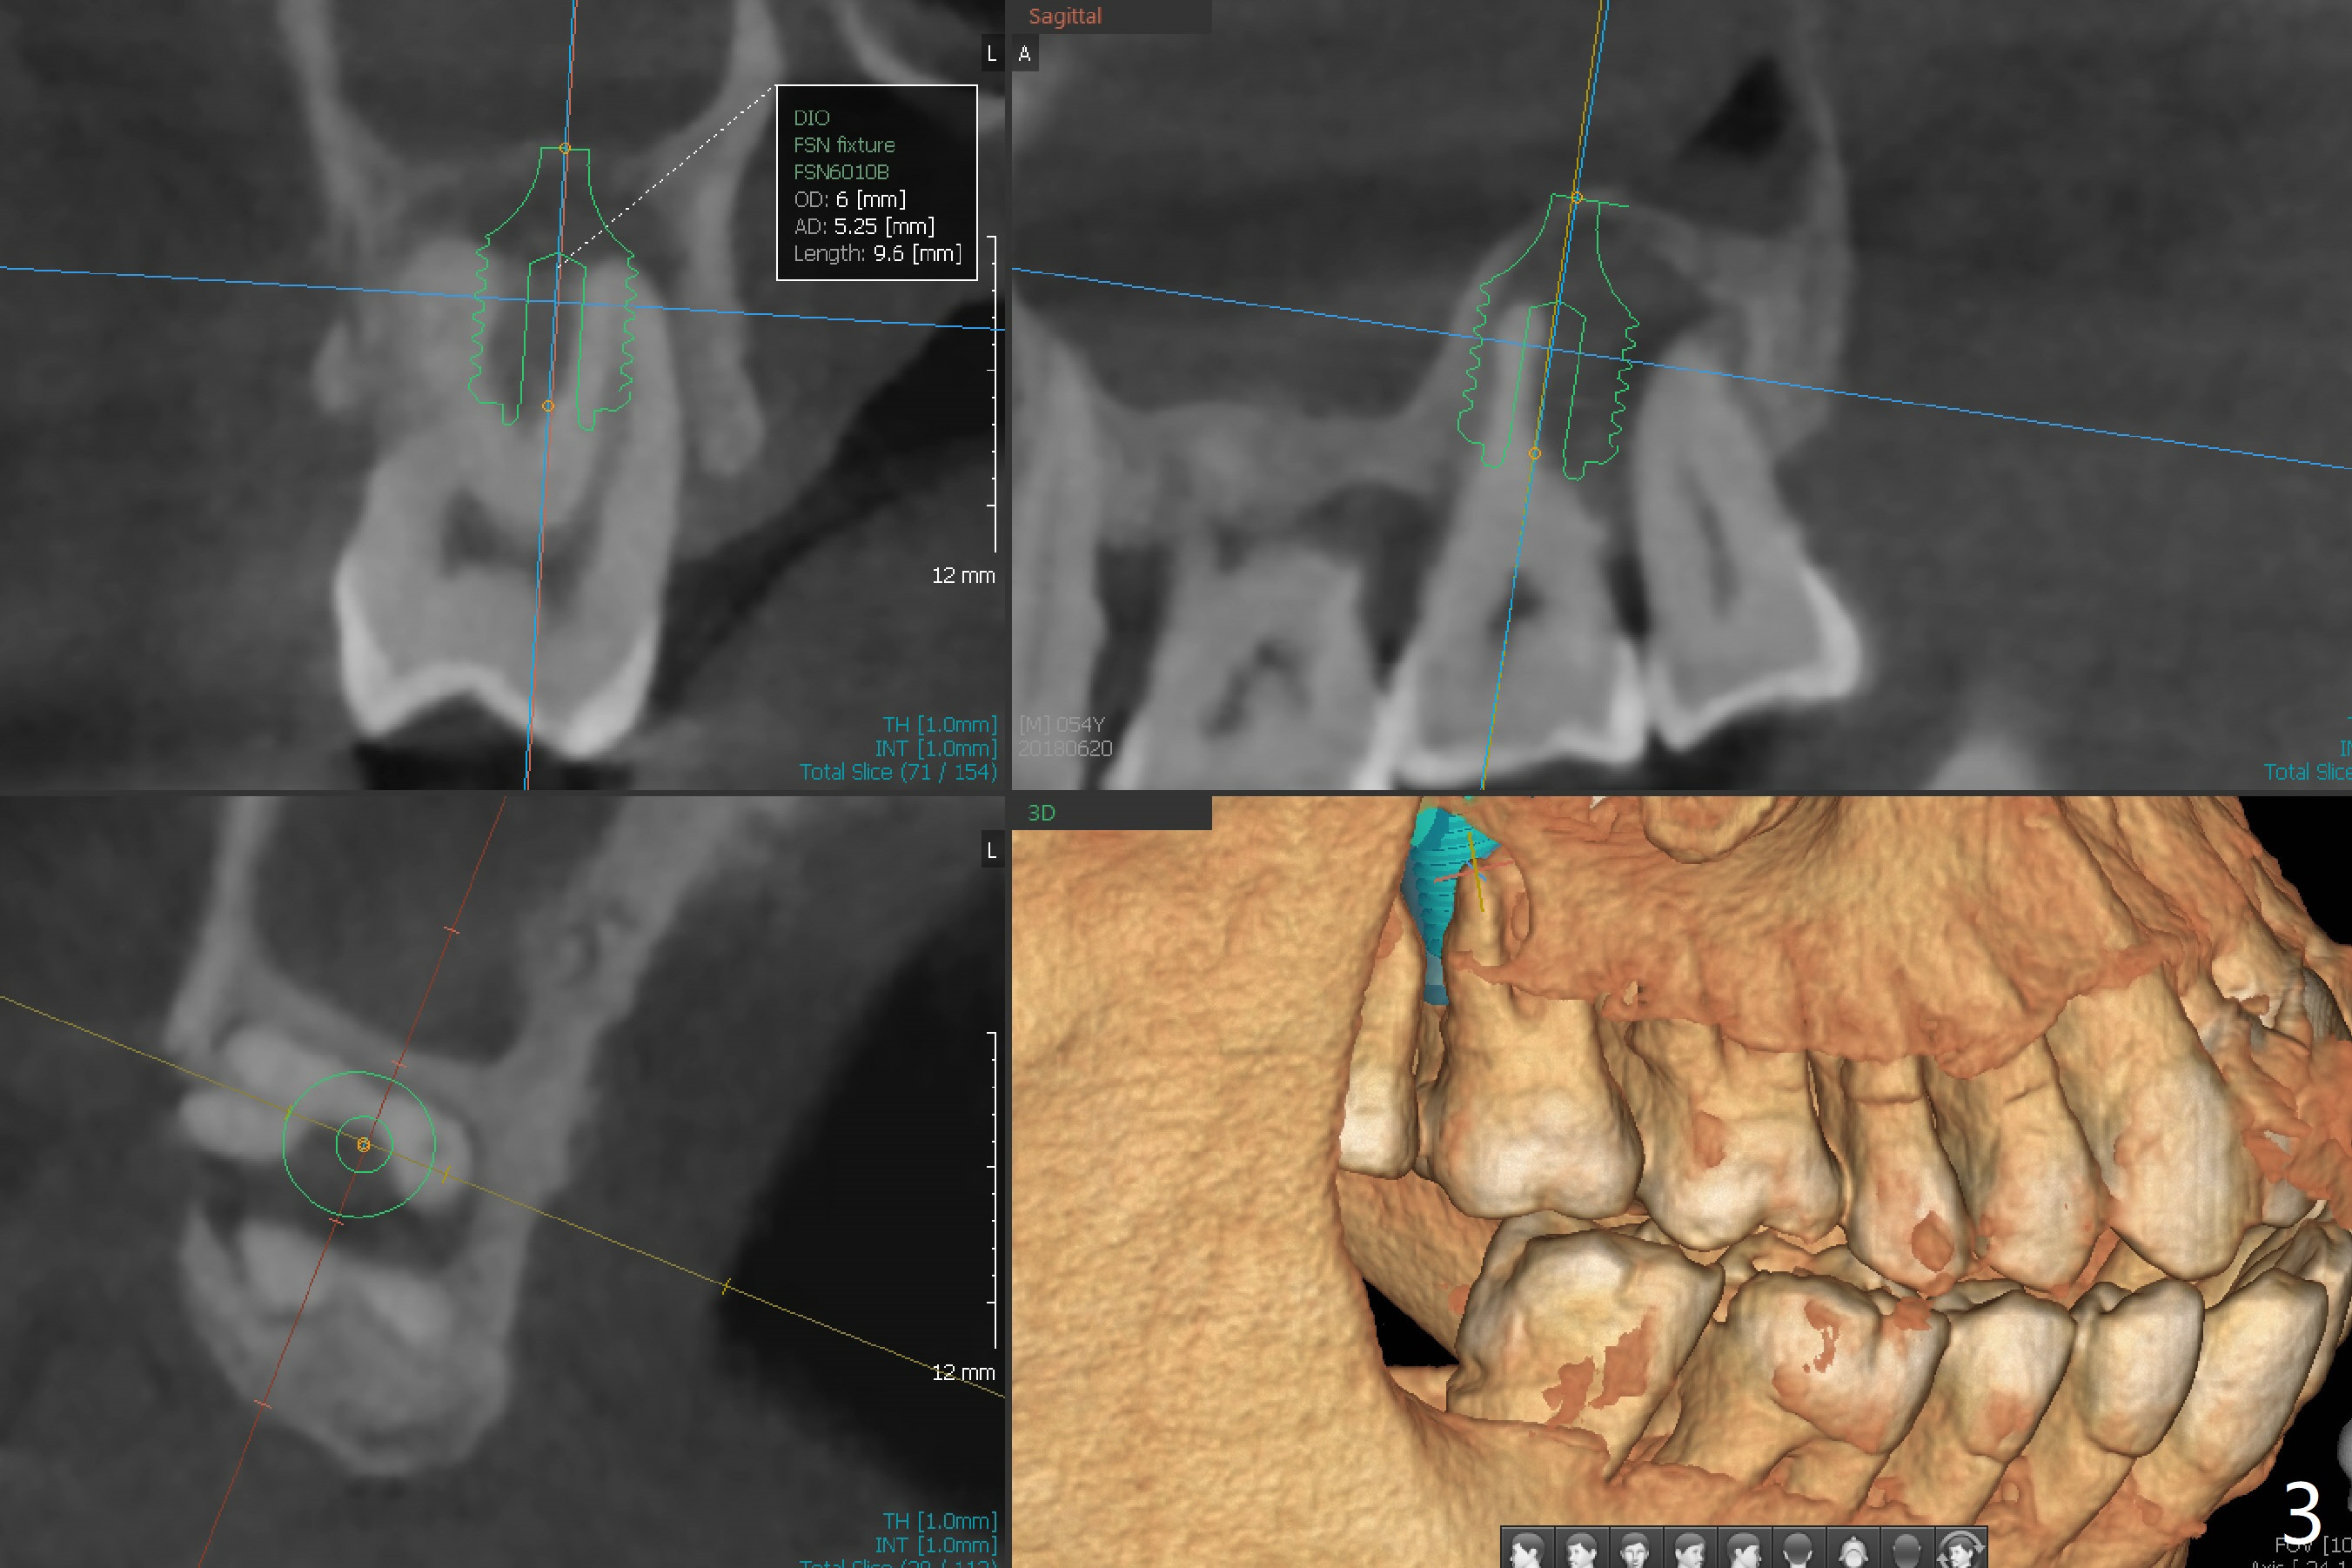

A 54-year-old man presents to office with a request to get a tooth back in the upper left posterior region (Fig.1 #14, wearing RPD). Upon examination, he feels that the tooth #2 is mobile, requiring more urgent care (Fig.2). The infection also involves the tooth #1. Extraction of the latter seems to be imminent. At either site, bone height is limited. Sinus lift is expected with PRF. Place an implant that just passes the sinus floor for stability, e.g., 5-6x10 mm at #2 (Fig.3), but not too long into the sinus. At the 2nd stage (Fig.4), use Magic drill with 2 mm stopper as a tissue punch. Then with 3 mm stopper start osteotomy, followed by Magic lifter, PRF/bone graft and dummy implant or tap. More bone graft and definitive implant. In fact the patient wants to have #14 implant first.